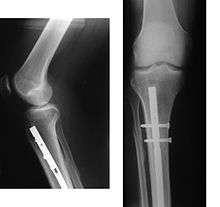

A bone fracture may be diagnosed based on the history given and the physical examination performed. Radiographic imaging is often performed, to confirm the diagnosis. Under certain circumstances, radiographic examination of the nearby joints is indicated in order to exclude dislocations and fracture-dislocations. In situations where projectional radiography alone is insufficient, Computed Tomography (CT) or Magnetic Resonance Imaging (MRI) may be indicated.

Immobilization

Since bone healing is a natural process which will most often occur, fracture treatment aims to ensure the best possible function of the injured part after healing. Bone fractures are typically treated by restoring the fractured pieces of bone to their natural positions (if necessary), and maintaining those positions while the bone heals. Often, aligning the bone, called reduction, in good position and verifying the improved alignment with an X-ray is all that is needed. This process is extremely painful without anesthesia, about as painful as breaking the bone itself. To this end, a fractured limb is usually immobilized with a plaster or fiberglass cast or splint which holds the bones in position and immobilizes the joints above and below the fracture. When the initial post-fracture edema or swelling goes down, the fracture may be placed in a removable brace or orthosis. If being treated with surgery, surgical nails, screws, plates and wires are used to hold the fractured bone together more directly. Alternatively, fractured bones may be treated by the Ilizarov method which is a form of external fixator.